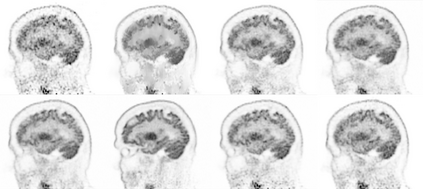

Due to various physical degradation factors and limited counts received, PET image quality needs further improvements. The denoising diffusion probabilistic models (DDPM) are distribution learning-based models, which try to transform a normal distribution into a specific data distribution based on iterative refinements. In this work, we proposed and evaluated different DDPM-based methods for PET image denoising. Under the DDPM framework, one way to perform PET image denoising is to provide the PET image and/or the prior image as the network input. Another way is to supply the prior image as the input with the PET image included in the refinement steps, which can fit for scenarios of different noise levels. 120 18F-FDG datasets and 140 18F-MK-6240 datasets were utilized to evaluate the proposed DDPM-based methods. Quantification show that the DDPM-based frameworks with PET information included can generate better results than the nonlocal mean and Unet-based denoising methods. Adding additional MR prior in the model can help achieve better performance and further reduce the uncertainty during image denoising. Solely relying on MR prior while ignoring the PET information can result in large bias. Regional and surface quantification shows that employing MR prior as the network input while embedding PET image as a data-consistency constraint during inference can achieve the best performance. In summary, DDPM-based PET image denoising is a flexible framework, which can efficiently utilize prior information and achieve better performance than the nonlocal mean and Unet-based denoising methods.